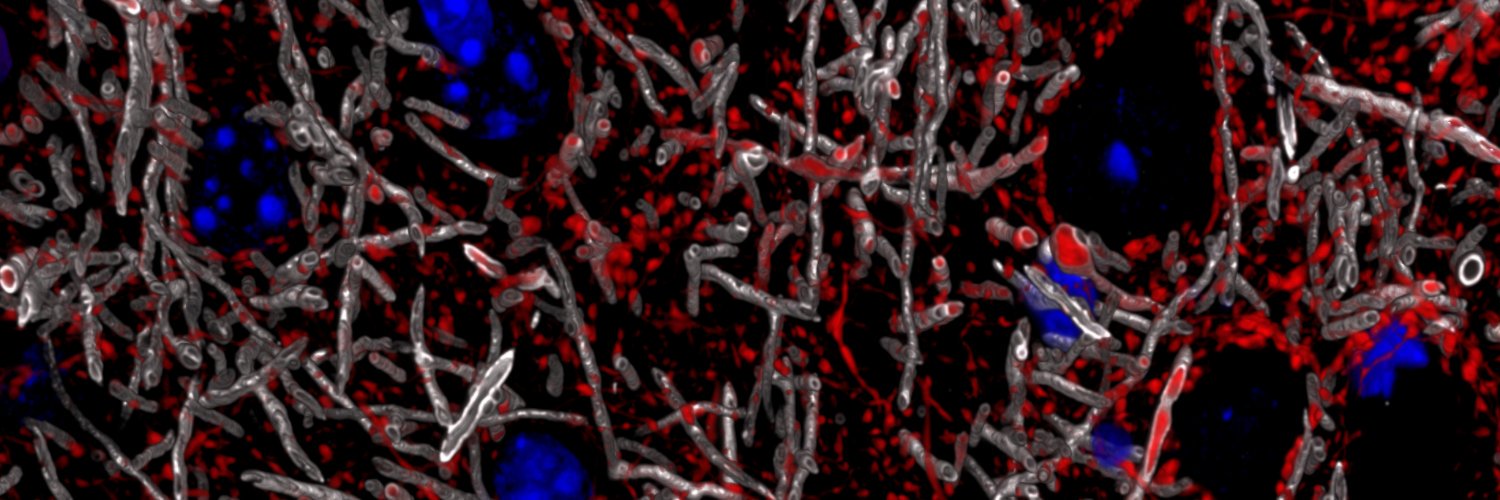

Happy #MicroscopyMonday! Going back to my roots with some amyloid in this 3D image 🤓🔬! It shows two different markers for amyloid pathology:

🔴Anti-Amyloid Fibrils OC;🟢Thioflaving S: a Dye for β sheet-rich deposits found in misfolding protein diseases. Surrounding this amyloid plaque are some very activated astrocytes (🔵Gfap). You can see some delineating a blood vessel nearby, passing in the middle of the amyloid plaque. @zeiss_micro